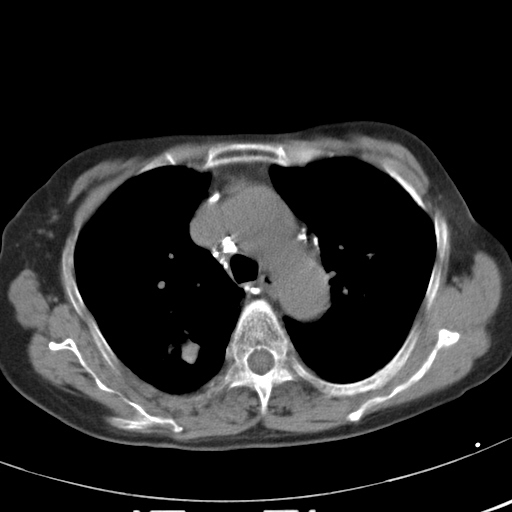

以下是引用hhcckk在2007-3-2 14:51:00的发言:[br]考虑结核球可能性大,依据[br]1病灶在下叶背段,结核的好发部位[br]2病灶内有大量的钙化,纵隔内有大量的淋巴结钙化[br]3重要的是半年前与现在相比无变化,假如是肿瘤的话不会这么‘善良’[br]4病灶周围卫星灶不明显,病灶有毛刺,胸膜凹陷,肿瘤不能完全排除,有条件的话最好做个活检

以下是引用liuyue在2007-3-2 17:15:00的发言:[br]1位置:右上叶后段[br]2性质:大分叶、粗长毛刺、条状斑片状钙化、纵隔多发淋巴结钙化,无强化,故考虑:肺结核灶(陈旧)